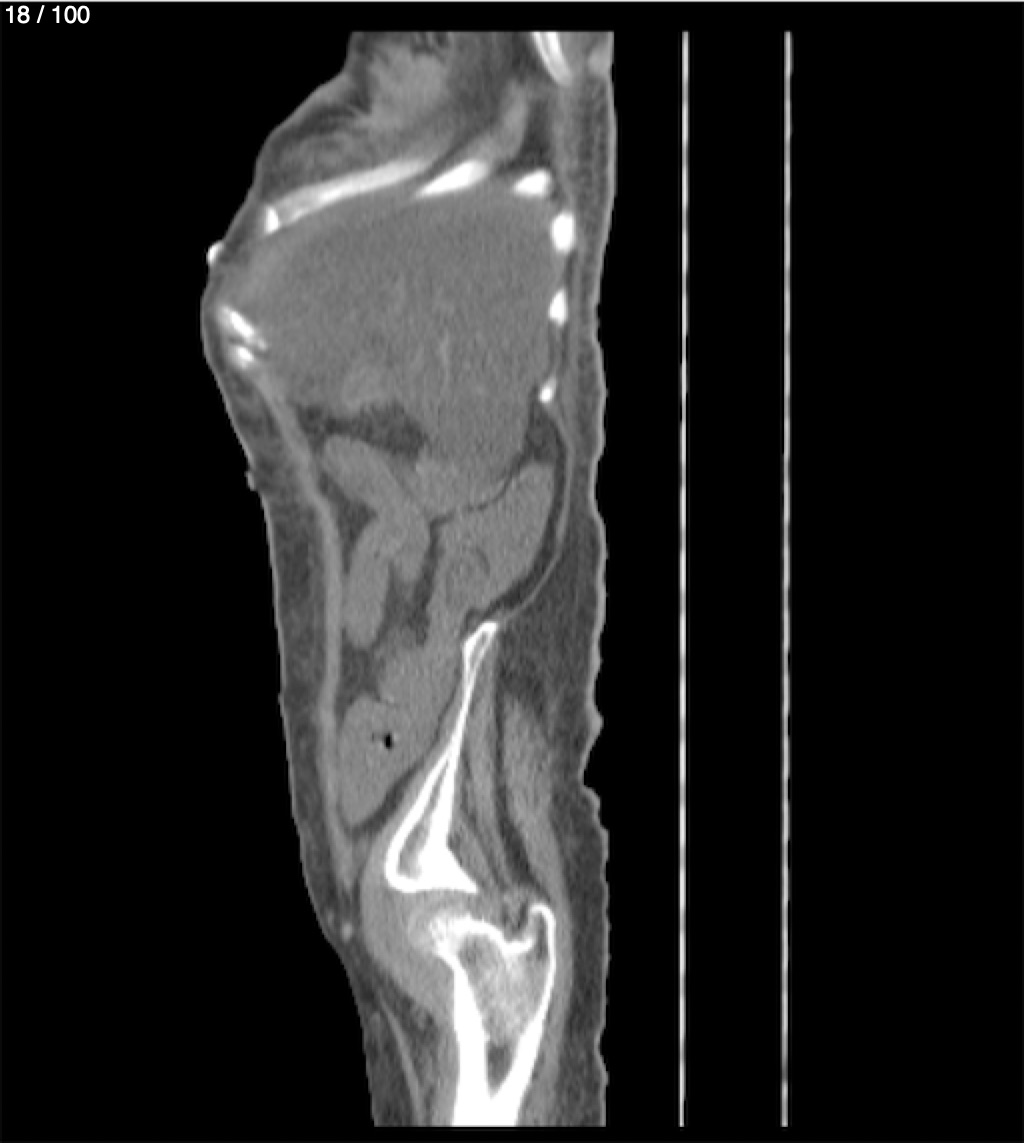

Hilda Geronimo Mendez 60A - T.C Abdomen Simple